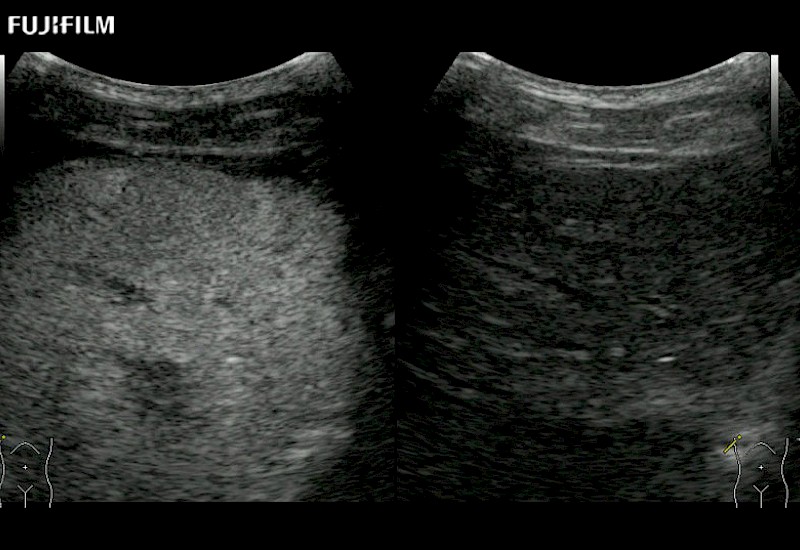

The ARIETTA 750 incorporates all of the proven technologies and functions that medical professionals have come to expect from Fujifilm Healthcare.

ARIETTA 750 is the definitive diagnostic ultrasound solution for any clinical setting - Private Office, Imaging Center, or Hospital. The ARIETTA platform provides the ultimate in clinical performance with its state-of-the-art features and large user-friendly display.

The ARIETTA 650 DI combines trusted Fujifilm Healthcare technologies and features tailored for surgical oncology.

Designed to meet the demands of surgeons, the ARIETTA 650 DI offers precise guidance. Its advanced capabilities and large, intuitive display offer accurate and efficient care in operating rooms and specialized surgical settings.